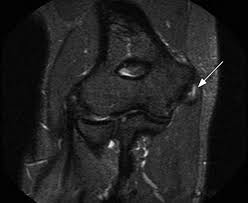

Imaging such as an ultrasound or MRI is also sometimes used to help diagnose golfer’s elbow, with an MRI being considered the ‘gold standard’ for diagnosis. In the case of golfer’s elbow, imaging is more often used to rule out other injuries that may be causing symptoms. However, should imaging be used to help diagnose golfer’s elbow, an MRI would reveal a thickened common flexor tendon sheath (Abbasi & Ahmad, 2024). This may be hard to identify on imaging if you’re unsure what to look for, so always ask for a second (or even third) opinion if you’re not sure.